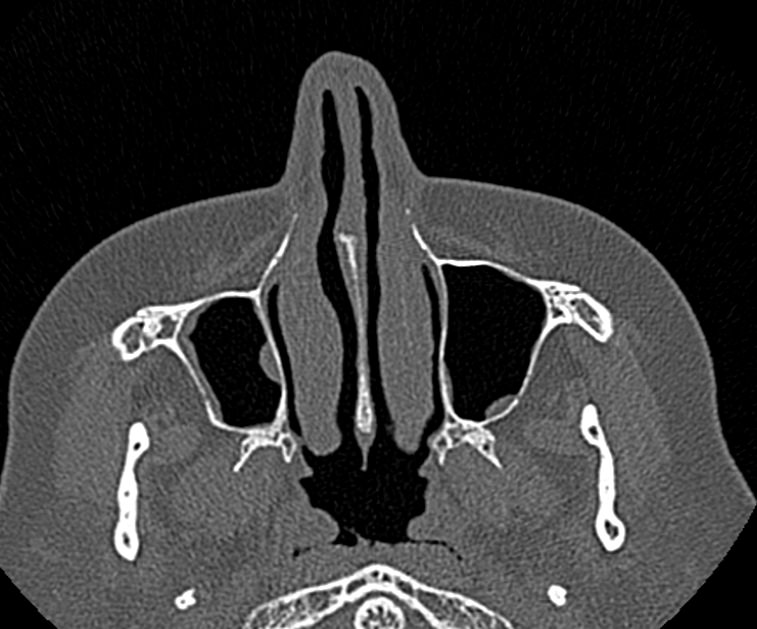

Золотым стандартом в диагностике патологических процессов пазух носа является мультиспиральная компьютерная томография, которая является быстрым безболезненным и неинвазивным (то есть без вмешательства в организм) способом исследования состояния синусов. Метод основан на проникающей способности ионизирующего излучения и получения изображений органов и тканей организма за счет разной степени поглощения ими рентгеновских лучей.

На основе полученных данных цифровые приложения томографов создают трехмерные реконструкции пазух носа, что позволяет оценить пространственное взаимоотношение анатомических структур и помогает в диагностике патологии околоносовых пазух.

Мультиспиральная компьютерная томография дает информацию о состоянии полости носа, носовой перегородки, степени воздушности околоносовых пазух, путей дренирования синусов, состоянии слезных каналов. Сканирование позволяет оценить толщину слизистой, наличие патологического содержимого в просвете пазух (уровня «жидкости»), выявить опухолевые образования. С помощью КТ можно провести точную диагностику травматических повреждений костей лицевого черепа, определить локализацию инородных тел, попавших в полости синусов.

С помощью объемной реконструкции можно перед оперативным вмешательством увидеть особенности анатомии ЛОР-органов, определить точное расположение патологического очага по отношению к окружающим тканям. Компьютерная томография помогает в диагностике аномалий развития придаточных пазух носа, слезоотводящих каналов.